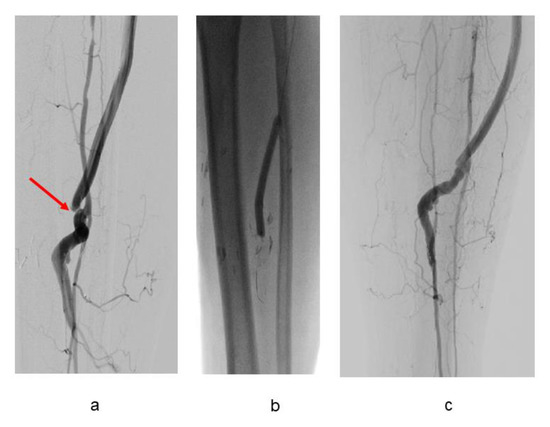

3.2. Bypass Configuration